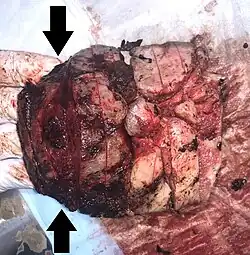

| Gross pathology of severe intervillositis, with dark red and soggy tissue. | |